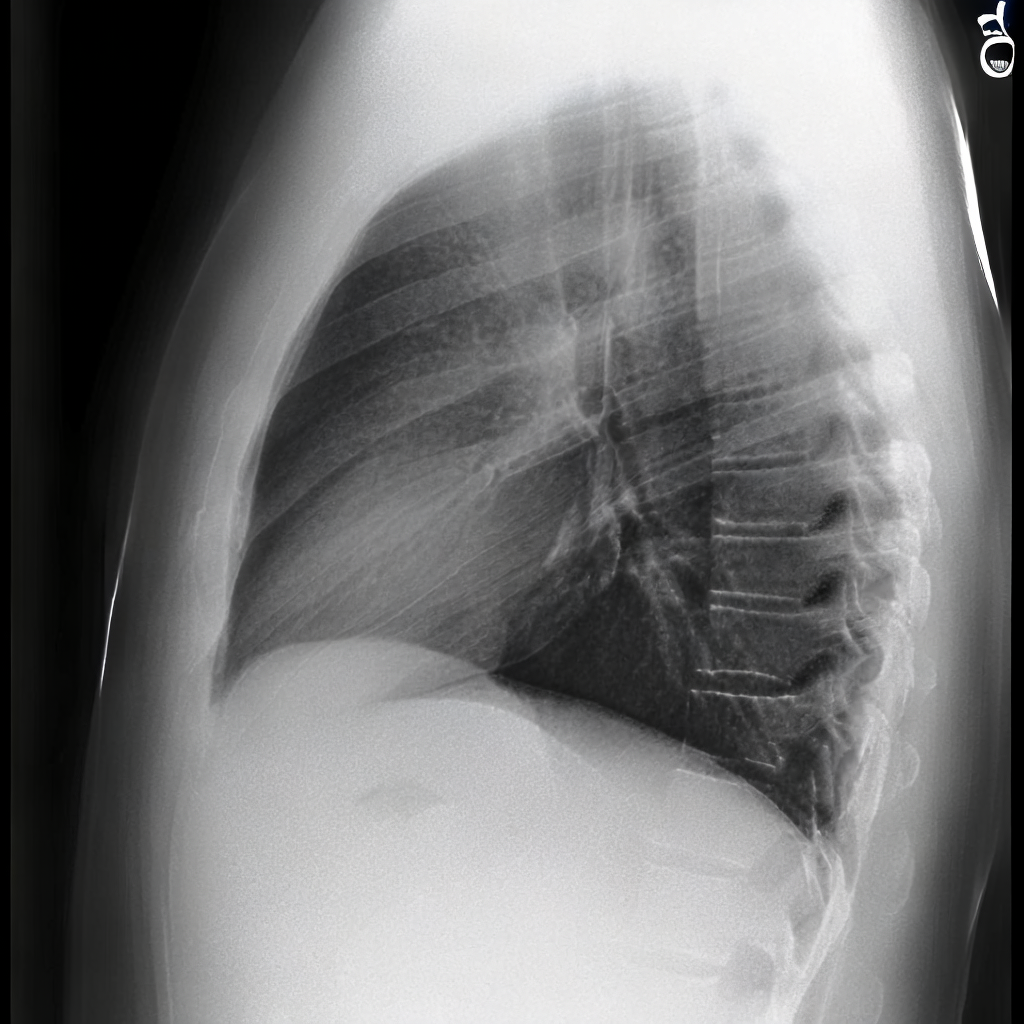

Diffusion models have recently gained significant traction due to their ability to generate high-fidelity and diverse images and videos conditioned on text prompts. In medicine, this application promises to address the critical challenge of data scarcity, a consequence of barriers in data sharing, stringent patient privacy regulations, and disparities in patient population and demographics. By generating realistic and varying medical 2D and 3D images, these models offer a rich, privacy-respecting resource for algorithmic training and research. To this end, we introduce MediSyn, a pair of instruction-tuned text-guided latent diffusion models with the ability to generate high-fidelity and diverse medical 2D and 3D images across specialties and modalities. Through established metrics, we show significant improvement in broad medical image and video synthesis guided by text prompts.

In this work, we focus on the ability of LDMs to generate novel datasets to overcome class imbalances traditionally associated with medical data, and potentially reduce the need for manual annotation of medical 2D and 3D data. We present MediSyn, a pair of text-guided latent diffusion models for broad medical 2D and 3D modality synthesis. To overcome the scarcity of labelled medical data, we leverage a vast corpus of more than 5 million image-caption pairs and 100,000 video-caption pairs collected from the public domain across numerous medical specialties, and integrate comprehensive natural language annotations to develop a pair of versatile diffusion models for the medical domain.

Our work, akin to Sagers et al. and Chambon et al. focuses on synthesizing multi-class medical datasets through text prompts. In their work, Chambon et al. adapt a pre-trained LDM, Stable Diffusion, on a corpus of chest x-rays (CXR) and their corresponding radiology reports to generate CXR displaying different disease states [29]. Similarly, Sagers et al. use DALL-E to synthesize skin lesions across all Fitzpatrick skin types [30].

Our findings demonstrate Medisyn’s remarkable ability to generate high-fidelity and diverse medical images, image sequences and volumetric scans across various medical subspecialties and imaging modalities. Other medical text-driven diffusion models, such as TauPETGen [42] for tau PET images and GenerateCT [43] for chest CT volumes, have proven successful in generating high-quality images that accurately depict anatomical features and clinical conditions. However, these models are constrained to a single imaging modality and anatomical region, thereby restricting their applicability. Moreover, they were trained on relatively small datasets sourced from a limited number of institutions, which could lead to more biased outputs. In contrast, Medisyn, having been trained on one of the largest publicly accessible medical image and video datasets to date, is equipped to synthesize data that cover numerous medical disciplines, population groups, and disease states. Leveraging our two models, we can synthesize new medical datasets as well as augment existing ones, potentially improving a wide array of medical machine learning tools, both general and specialized. Additionally, our models can minimize the need to repeatedly fine-tune on specific datasets for generating different imaging modalities, thus reducing computational costs for academic labs.